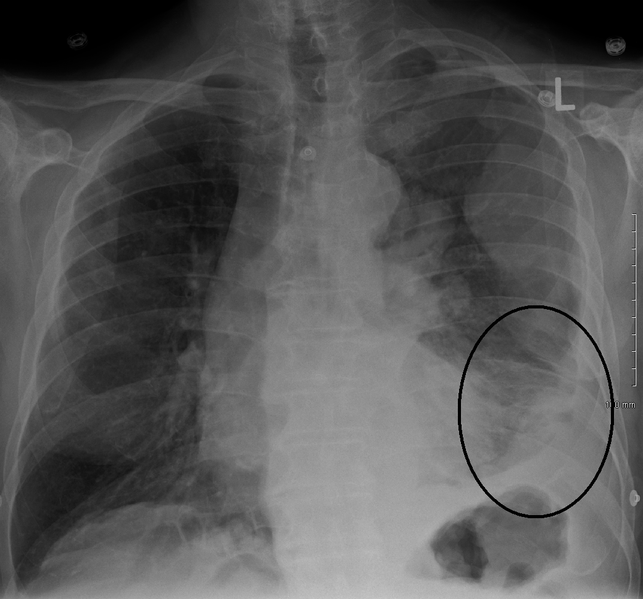

Pleural plaques and asbestos. Pleural plaques are deposits of fibrous tissue that develop in the chest cavity as a result of asbestos exposure. These deposits usually are found on the parietal pleura the membrane that lines the chest wall. Its opposite, the. Pleural disease clevelandclinicmeded. Pleural disease online medical reference covering definition through treatment. Authored by raed a. Dweik of the cleveland clinic. Pleural effusion is usually the. Pleural plaques and asbestos mesothelioma center. Pleural plaques are by far the most common indication of significant exposure to asbestos. Characterized by areas of fibrous thickening on the lining of the lungs (pleura) or diaphragm, the condition typically arises 20 to 30 years after asbestos. Pleural plaques and asbestos mesothelioma center. Pleural plaques asbestos. Explore related search results. Search for pleural plaques asbestos info. Try a new search on alot! Fibulin3 as a blood and effusion biomarker for pleural. Background new biomarkers are needed to detect pleural mesothelioma at an earlier stage and to individualize treatment strategies. We investigated whether fibulin3. Pleural plaques mesothelioma. Pleural plaques are areas of thickened tissue in the pleura, most often caused by asbestos. Pleural plaques are the most common signs of damage to the chest cavity related to asbestos exposure. Plaques may not develop until many decades after exposure to asbestos.

Solid pleural lesions american journal of roentgenology. Benign pleural thickening is defined as a continuous process more then 5 cm wide, 8 cm in craniocaudal extent, and 3 mm thick, all of which are best measured on ct. Pleural mesothelioma asbestos news. Pleural plaques first appear around 20 years after a person is exposed to asbestos. Prior to the 1970s, when asbestos regulations came into effect, countless workers. Asbestosrelated diseases copd, pleural effusion & more. All the information you need to know about pleural plaques for more help please call the national asbestos helpline 0808 250 6783. Pleural plaques asbestos alot. Search for pleural plaques asbestos info. Try a new search on alot! Causes of pleural plaques, diagnosis, treatment and asbestos. Inside your chest area, there is a twolayered membrane. One layer surrounds your lung and the other lines your rib cage. This membrane is known as the pleura. Pleural plaques asbestos webcrawler. Pleural mesothelioma is a form of cancer that develops in the pleura, or outer lining of the lungs. The mesothelium is a large membrane of tissue that provides a. Asbestos public health. Information about the health risks of asbestos and the benefits veterans are eligible to receive based on exposure during service. Asbestos justice claims asbestosis and mesothelioma. Looking to make a claim for asbestosis or mesothelioma? Our law firm can help you win compensation, make a claim with our no win no fee solicitors.